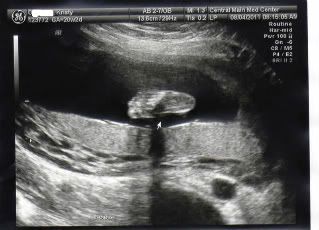

a very healthy baby. Here are some pictures from my A/S this morning. Still Team Green although the tech said the baby was very eager to show the goods. We looked away!

Here is peanut's foot